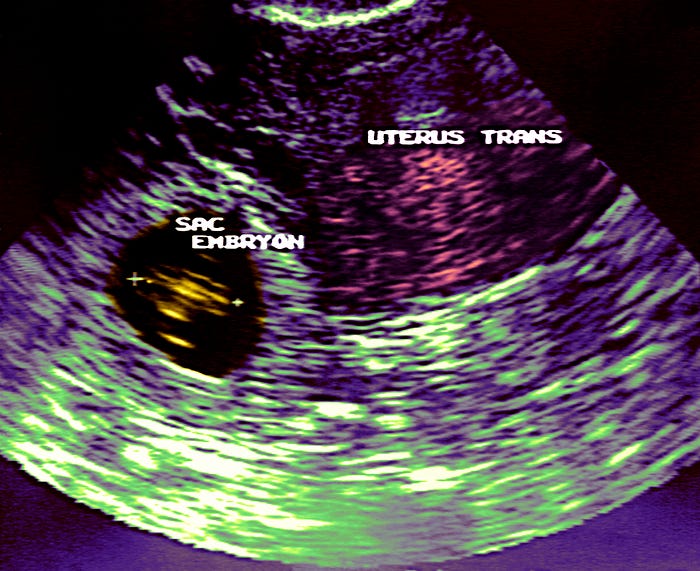

This week, the conservative publication the Federalist published an article by Georgi Boorman arguing that women should carry ectopic pregnancies to term, and urging doctors to take a “watchful waiting” approach rather than end the dangerous pregnancy. While Boorman acknowledged that an ectopic pregnancy is life-threatening, she still scolded women who were putting fears of their own health above the well-being of their unborn children and falsely suggested the risk wasn’t all that great. “[I]s that very small chance [of dying] enough to prompt you to suffer through purposely destroying your own child?” Boorman asks.

But this isn’t just about one article. Earlier this year, an Ohio Republican claimed in a bill that ectopic pregnancy can be treated by “re-inplant[ing] the fertilized ovum into the pregnant woman’s uterus.” No such procedure exists.

The truth is that ectopic pregnancy is the leading cause of maternal death in the first trimester — a fact that makes conservative claims to the contrary so very dangerous. The anti-abortion movement wants us to ignore science, medicine, and doctors; better that we cross our fingers and hope that a woman won’t die. As Daniel Grossman, a reproductive services professor at the University of California, San Francisco, told Vox, “It is really malpractice to watch a patient who is at risk for a tubal rupture from an ectopic pregnancy,” without offering an abortion.